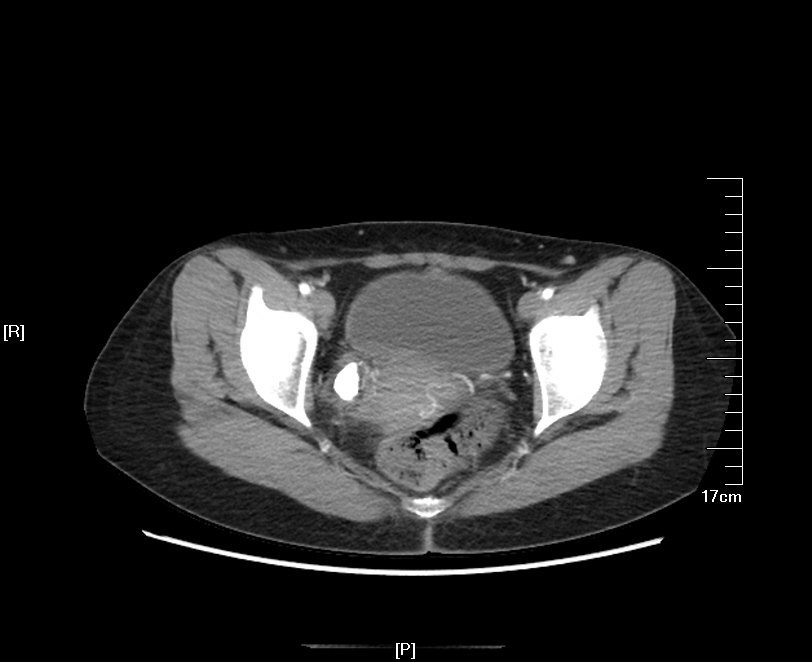

2016年04月手术患者,女性,32岁,昆山人,五年前曾因右输尿管结石引起肾绞痛于当地消炎补液解痉排石处理,疼痛缓解后未于重视,其间从未予复查,2周前出现右腰痛,与当地诊所就诊后予以震波碎石无效,并出现发热,急诊来我院就诊,CT:右肾萎缩,右侧肾脏积水,右侧输尿管多发结石形成石街约4.5*1.5cm,GFR:右侧17.2ml/min,左侧43.2ml/min。因左侧健肾代偿,肾功能正常:Cr 132umol/L;术前诊断:右输尿管下段多发结石 右肾萎缩 肾功能不全,鉴于右输尿管结石梗阻时间太长,肾功能不全,已处于失代偿期,最终也只能行右侧输尿管下段切开取术,解除输尿管下段梗阻,尽可能保护已经萎缩的肾脏,该患者预后不良。

增强CT检查提示:右侧肾脏积水,右肾萎缩,右输尿管下段多发结石

KUB提示右输尿管下段结石呈石街样排列,引起右输尿管完全梗阻,导致右肾萎缩